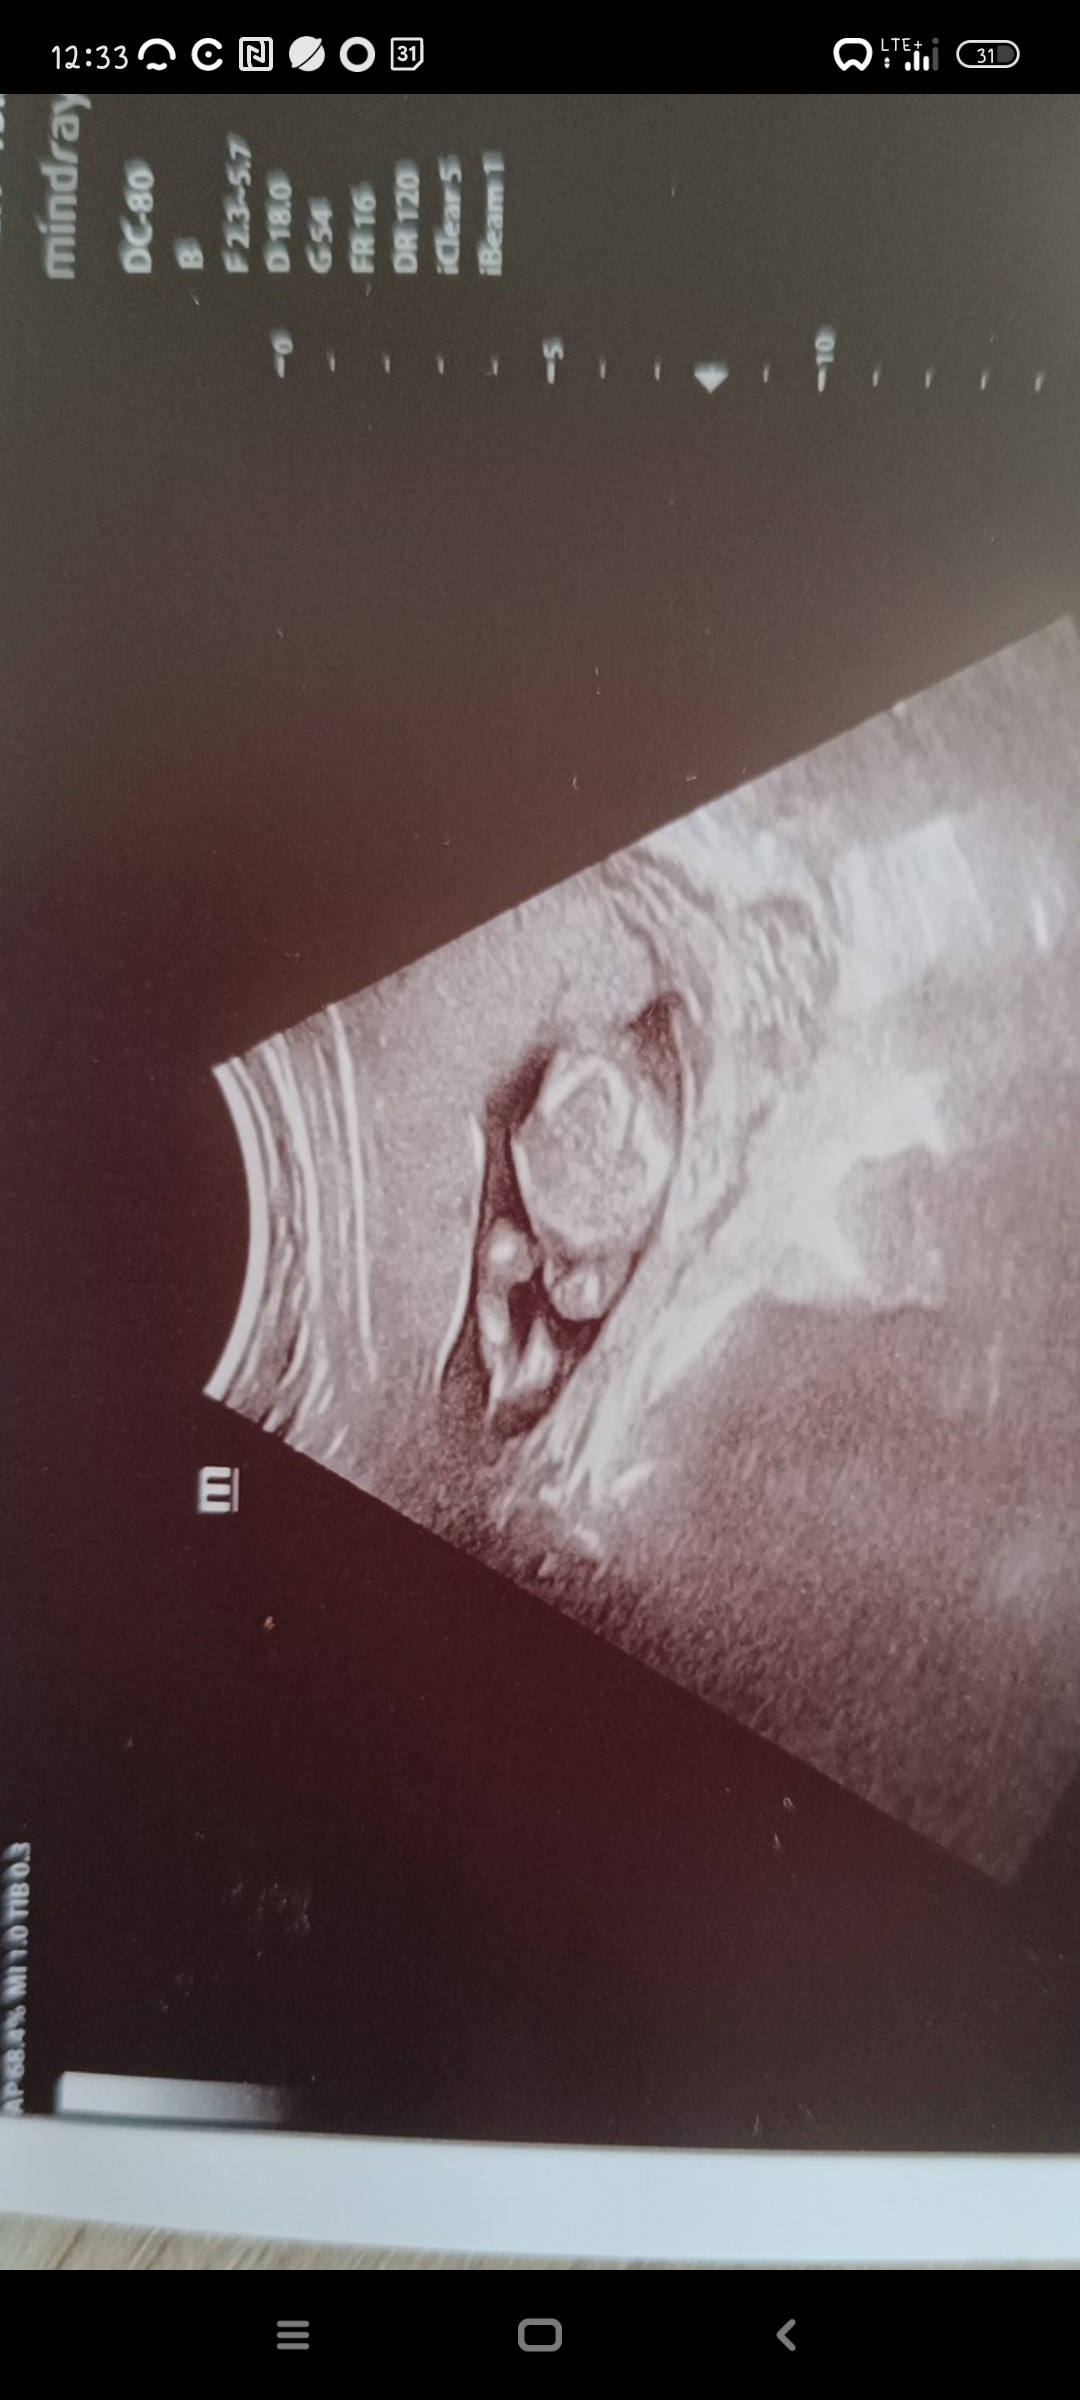

Jestem 15+1 tc., dzisiaj miałam USG, lekarz na podstawie tego co jest na zdjęciu powiedział że 90% chłopiec. Mam w domu 5 latka, który oszalałby z radości, ale boje się mu powiedzieć, bo co jeśli te 10% nagle się powiększy i okaże się że to tylko wyrostek płciowy a nie pe**s?